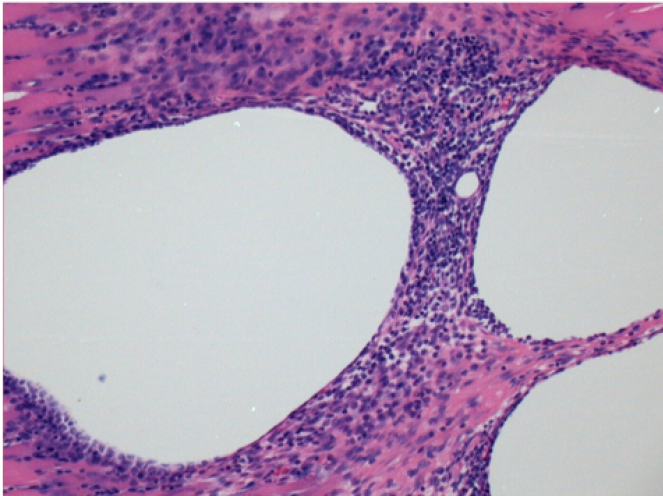

10 giorni dopo iniezione di Endopeel

Scatola Nr 2

- 10 giorni dopo iniezione 0.1ml di Endopeel nel muscolo pretibiale destro (Dx).

- Si osserva formazioni di vacuole , le quali circondate da linfociti.

- Le quali Vacuole sono differenti dal tessuto necrotico.

- La presenza di linfociti é correlata alla permeabilità delle membrane cellulari.

Sx : Controllo-100x-Giorno10

Dx:100x-Giorno10

Dx :200x-Giorno10

Dx :400x - Giorno10